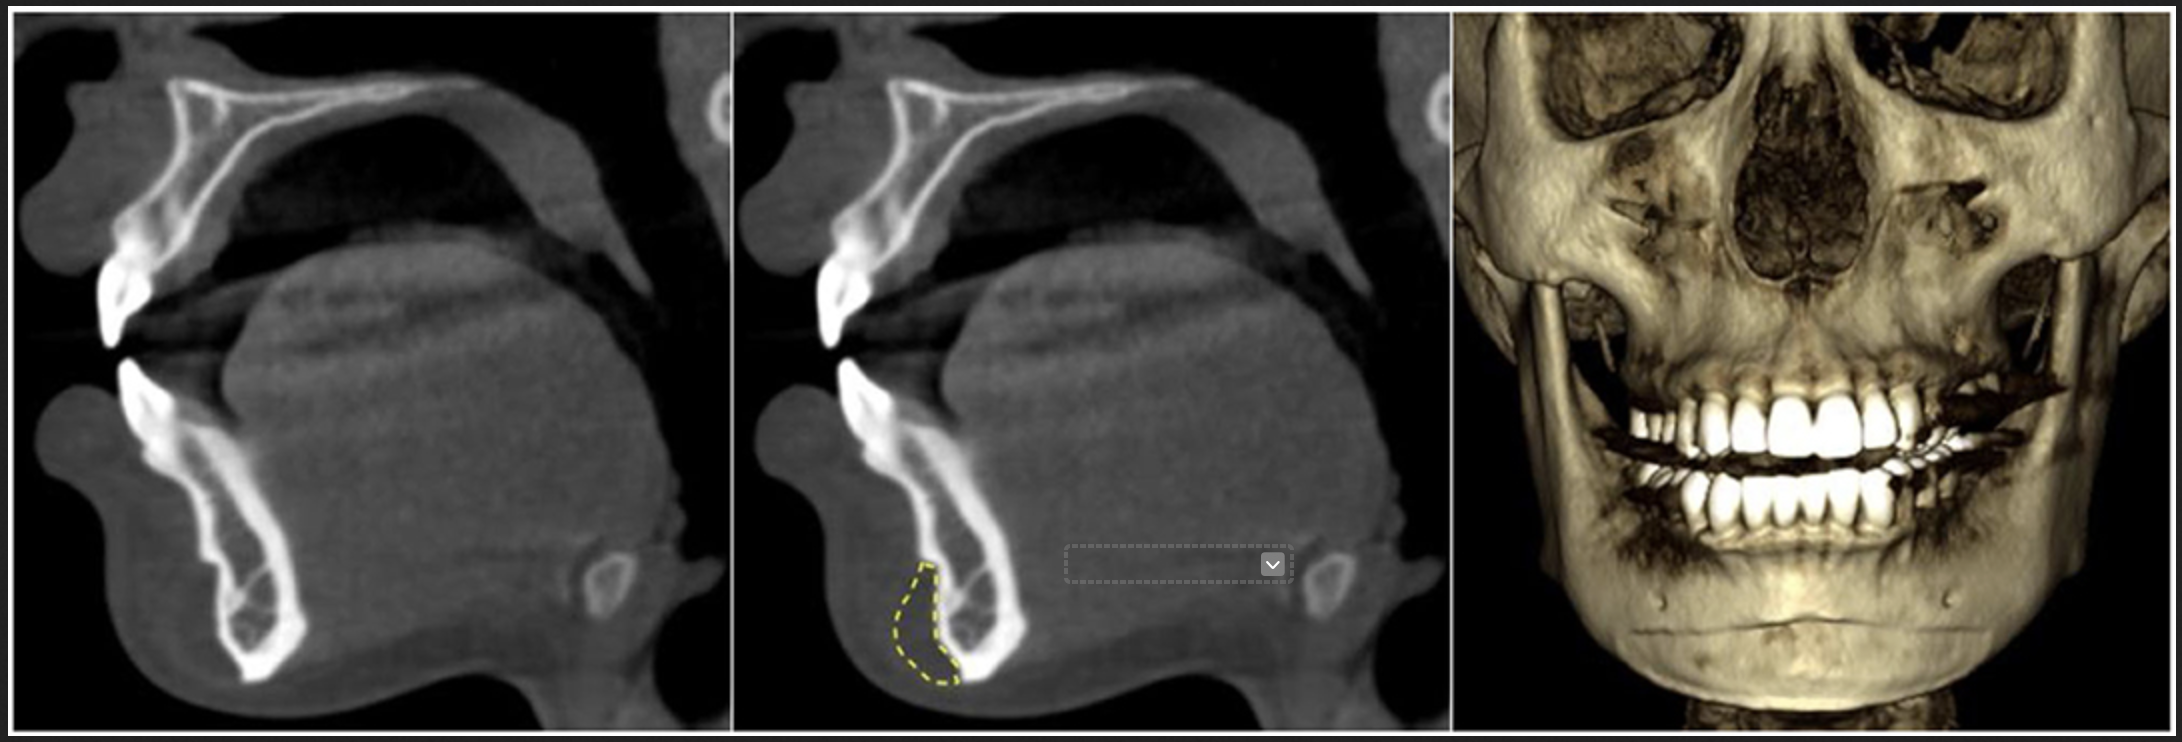

Traditional 2D X-rays provide limited information for modern implant and maxfax surgery. CBCT provides a 3D view of the jaws, teeth and surrounding structures, which can be invaluable when planning:

To visualise the jaw angle, jaw body and ramus in three dimensions.

To ensure implants follow the natural contours of the jaw and avoid critical areas such as the mandibular canal (where the inferior alveolar nerve runs).

At 3Beam, maxillofacial surgeons can request maxfax full-head CBCT scans when they need a comprehensive view of the facial skeleton for complex planning.